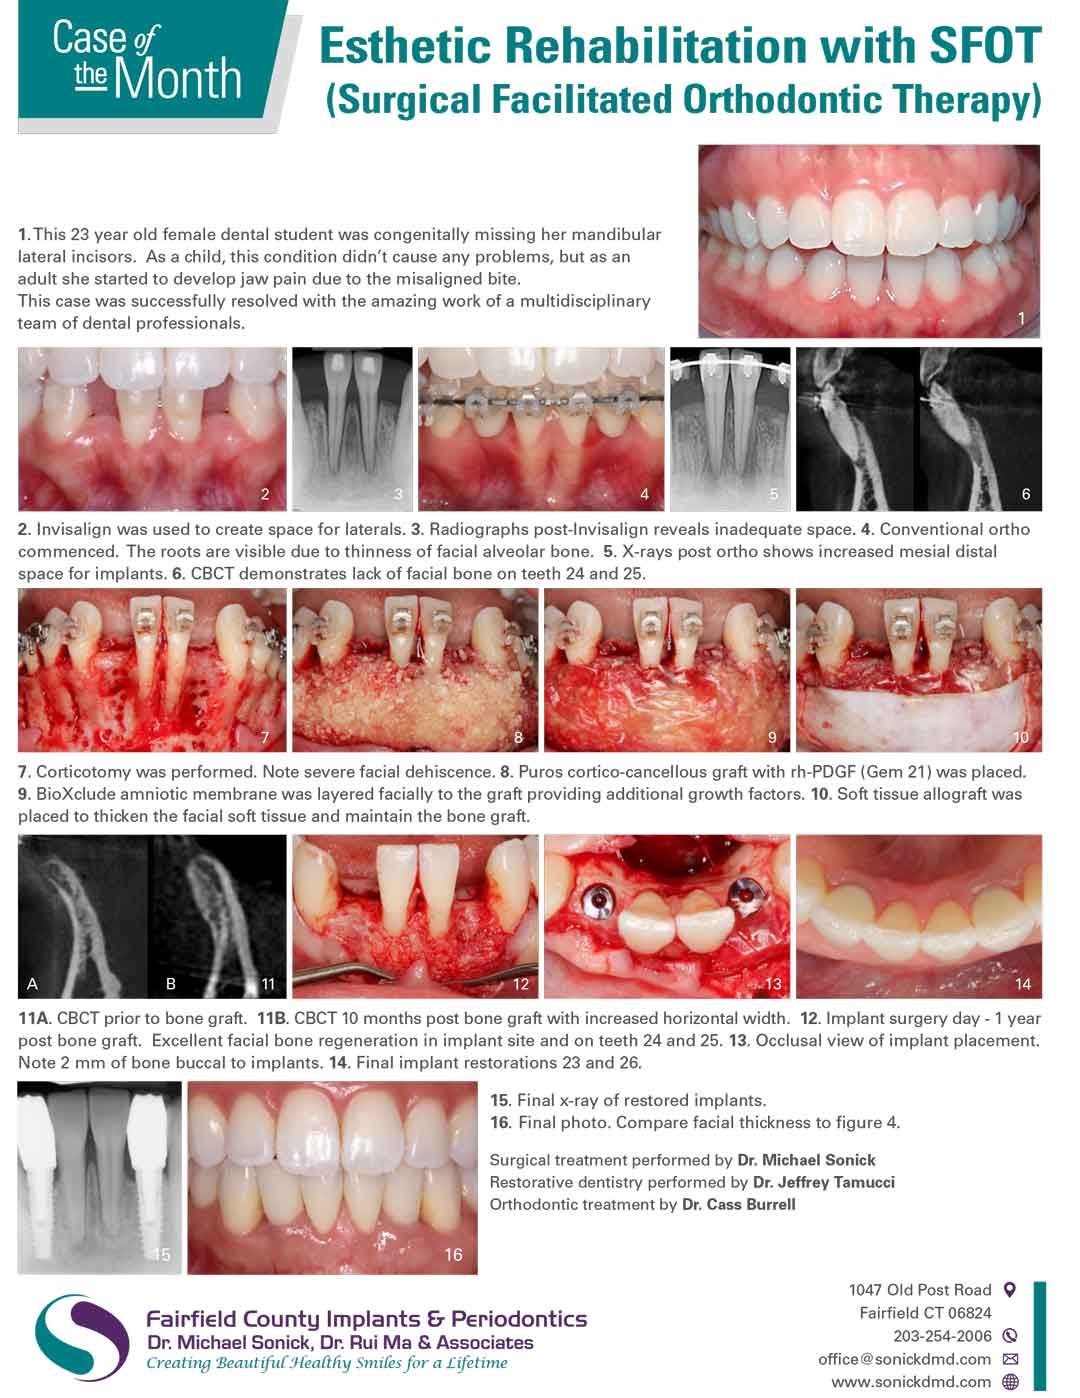

Case of the Month